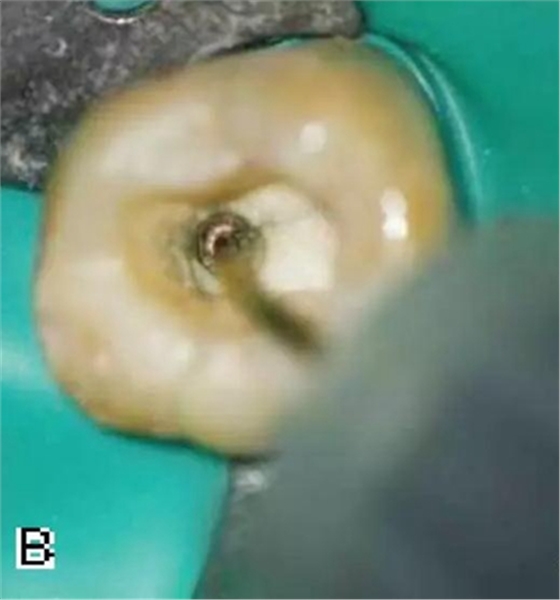

4、放置主尖及糊劑

將主尖的尖1/3 部分蘸一薄層根充糊劑,緩慢插入根管內(nèi),并左右旋轉(zhuǎn)主尖,以將根充糊劑均勻涂布于根管壁上,如圖4所示。

圖4 放置主尖及糊劑,A.放置主尖及糊劑 B.X線片下示主尖及糊劑的放置